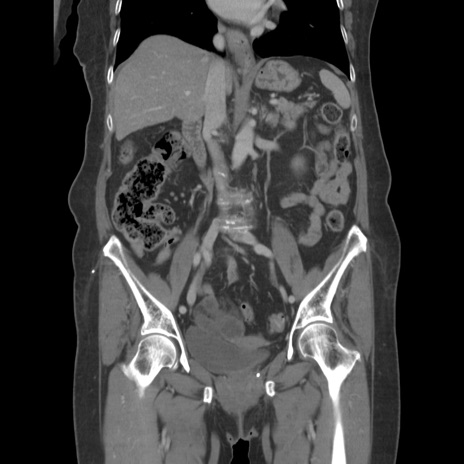

症例19(冠状断像)

【症例】80歳代女性

【主訴】下腹部痛

【現病歴】約8時間前より下腹部痛の出現あり、救急外来受診。

【既往歴】両側付属器切除

【身体所見】意識清明、下腹部正中に手術痕あり、その部位に一致して圧痛と反跳痛あり。腸蠕動音は亢進。

【データ】WBC 9300、CRP 0.15